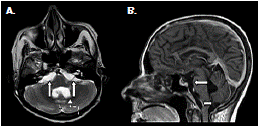

Ante la sospecha de vómito de origen central, se practicó una resonancia magnética cerebral que evidenció múltiples dilataciones de las cisternas y obstrucción del cuarto ventrículo (figura 3) y (figura 4); el líquido cefalorraquídeo tenía aspecto claro, 13 mg/ dl de proteínas, 73 mg/dl de glucosa, no presentaba leucocitos, y se registraron 3 eritrocitos por mm3; la tinción de Gram y el cultivo para bacterias resultaron negativos. Asimismo, se hizo una exploración del cuarto ventrículo por craneotomía suboccipital, mediante la cual se detectó aracnoiditis con obstrucción del agujero de Magendie, e inflamación aguda y crónica confirmada por biopsia. Se diagnosticó, entonces, vómito incoercible de origen central, secundario a neurocisticercosis racemosa (sic) y obstrucción del cuarto ventrículo, probablemente por aracnoiditis grave.

Según los hallazgos en las imágenes de resonancia magnética cerebral, los casos informados se clasificaron como neurocisticercosis extraparenquimatosa con quistes racimosos en el espacio subaracnoideo asociados a la intensa reacción inflamatoria (figura 1), (figura 4).

En los dos casos que se presentan, la neurocisticercosis racemosa (sic) se acompañó de hidrocefalia y aracnoiditis; en el primer caso, además, se detectó vasculitis de la arteria cerebral media derecha en sus porciones proximales adyacentes a las cisternas de la base y la silviana derecha, relacionada con la presencia de cisticercos (figura 1). En el segundo caso, se detectó dilatación y obstrucción del cuarto ventrículo por aracnoiditis (figura 3), hallazgo que explica la causa del vómito incoercible, debido a su estrecha relación anatómica con el área postrema (control del vómito).